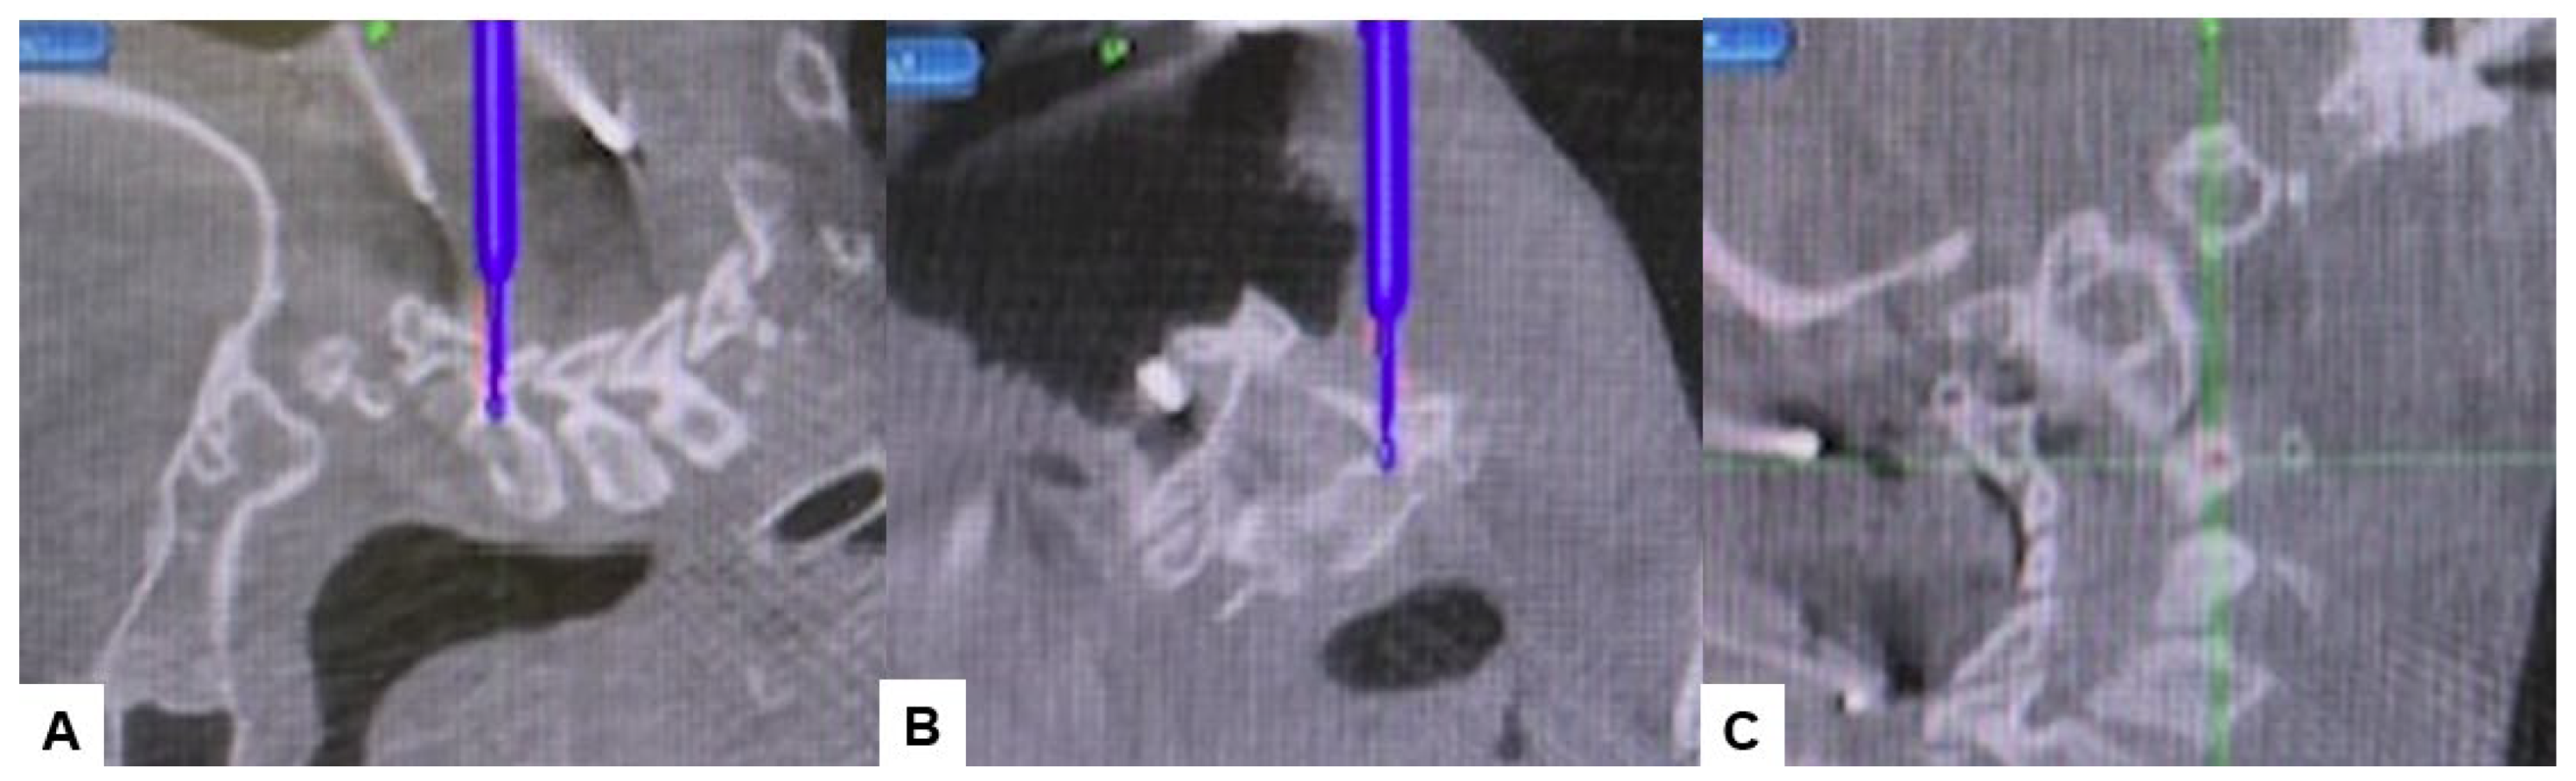

2.4. Surgery